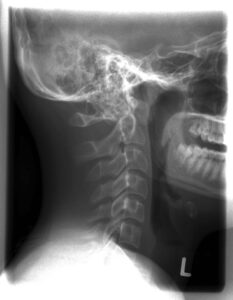

Röntgen 2:

ap: Al +/-, bds anterior,

seitl: Clivusverkürzung (Platybasie) und Dens recurvatus, Atlas grenzwertig superior, hintere Atlasbogenhyperplasie, vordere Atlasbogenhypoplasie

ALF?, Foramen arcuale